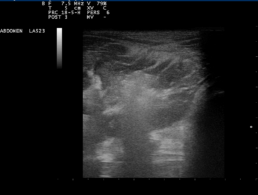

In der sonographischen Untersuchung des Halses stellte sich die ventrale Halsmuskulatur deutlich aufgelockert mit diffus hyperechogenen Bereichen (Abb. 1) dar. Es konnten keine pathologischen Befunde erhoben werden.

Abb. 1: ventrale Halsmuskulatur: deutlich aufgelockert Struktur mit diffus hyperechogenen Bereichen